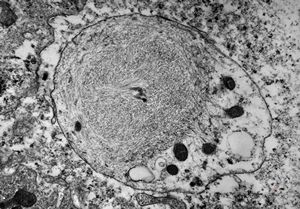

M,10y. | herpetic encephalitis